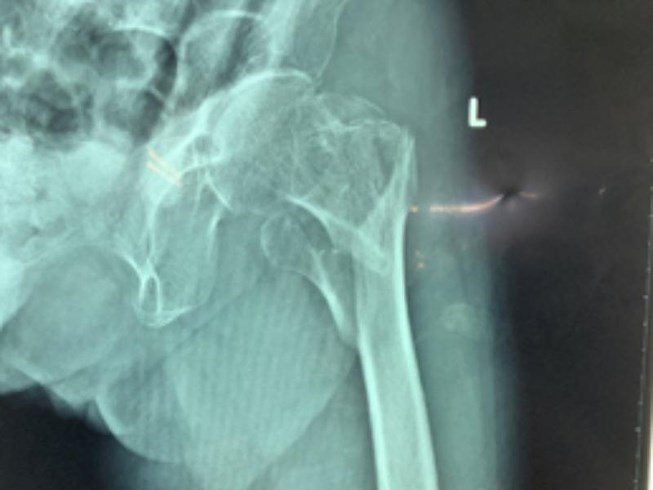

“Bệnh viện (BV) Chấn thương-Chỉnh hình TP HCM vừa phẫu thuật nối xương gãy kín nhiều mảnh ở đùi trái cho cụ bà NTH (101 tuổi, tỉnh Đồng Nai)”. Sáng 20/12, bác sĩ (BS) Võ Hòa Khánh, Trưởng phòng Quản lý chất lượng BV Chấn thương-Chỉnh hình TP HCM, cho biết thông tin trên.

Sau khi chụp X-quang, các BS kết luận đùi trái bà H. bị gãy nhiều mảnh xương kín. Các BS đã tiến hành phẫu thuật nối các mảnh xương gãy với nhau. Hiện cụ H. có thể sử dụng khung hỗ trợ để đi lại.

BS Khánh cho biết đây là trường hợp gãy xương phức tạp trên cơ địa bệnh nhân già yếu 101 tuổi có bệnh lý nội khoa (tăng huyết áp). Do vậy rất dễ xảy ra các biến chứng như viêm phổi, thuyên tắc phổi do nằm bất động lâu ngày và dẫn đến tử vong.